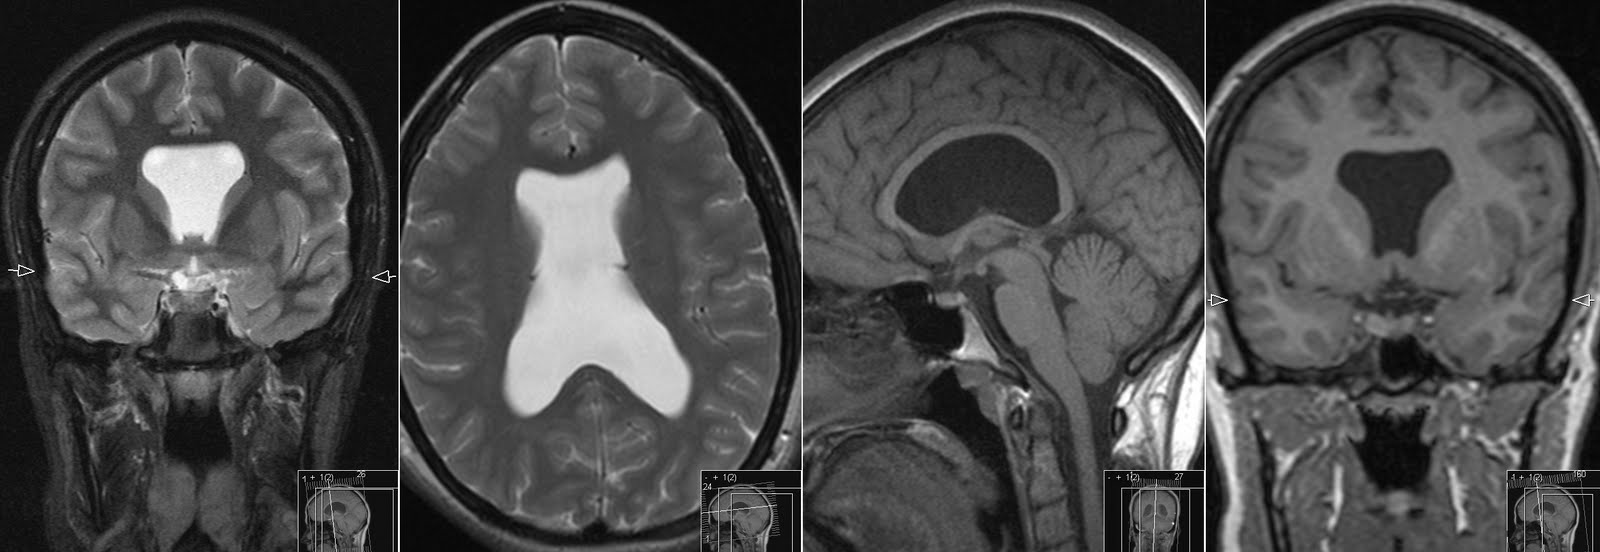

Прозрачная перегородка кт

Прозрачная перегородка кт 115 фотографий